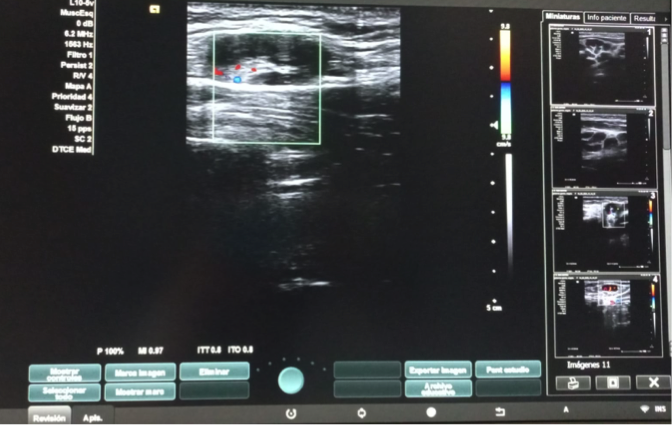

Hallazgos ecográficos

Dos adenopatías en territorio laterocervical derecho, con hilio central y doppler positivo, alguna con diámetro transversal superior al longitudinal, de probable origen reactivo y una adenopatía supraclavicular sin hilio central y con vascularización generalizada.